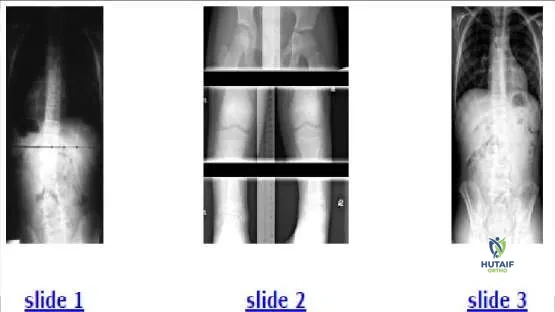

A 12-year-old boy presents for evaluation of a spinal curvature (Slide 1). Which of the following is the most likely cause of the spinal curve:

This patient has a 2.5 cm shortening of the left lower extremity, which can be seen from the uneven pelvic height on the radiograph. The shortening produces a compensatory curve. No rotation is present within the curve. Scanogam (Slide 2) documents the inequality. When the patient stands on a 2.5-cm lift, the curve is eliminated (Slide 3).